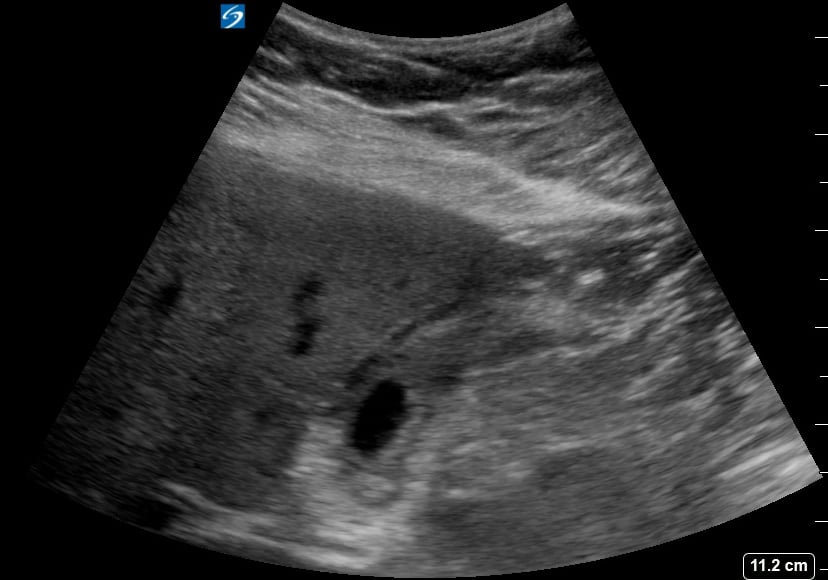

Pericholecystic fluid, in abdominal ultrasound, refers to an abnormal collection of fluid surrounding the gallbladder. Its presence is a key indicator of gallbladder inflammation, commonly seen in acute cholecystitis, a condition causing severe abdominal pain. Sonographers meticulously assess this fluid for its location, amount, and characteristics to aid in accurate diagnosis.

This fluid accumulation is a crucial diagnostic sign for healthcare professionals. Early detection via ultrasound helps guide timely medical intervention and treatment strategies, preventing further complications related to gallbladder disease and improving patient outcomes in abdominal imaging.